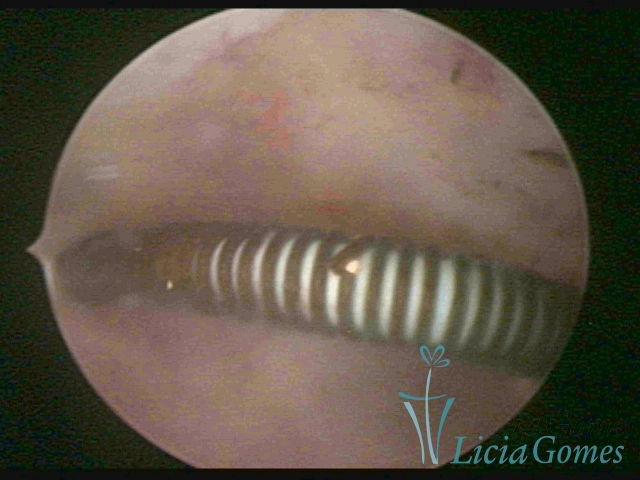

Canal cervical com fio do DIU